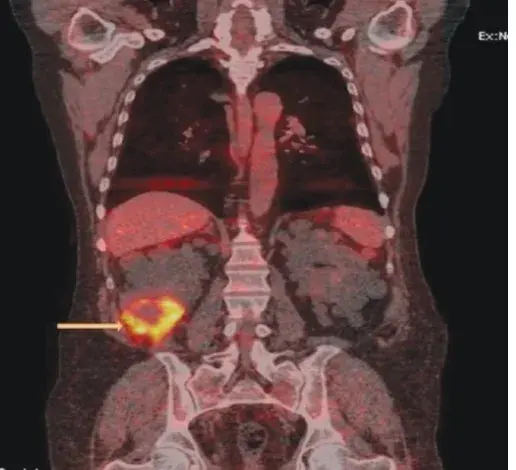

Radiografia e TC de tórax mostraram um derrame pleural volumoso a direita (imagem abaixo).

A-Rx de tórax indicando derrame pleural volumoso a direita. B-Drenagem de liquido quiloso. C-TC tórax com radioisótopo radioisótopo 99mTc indicando vazamento linfático hemitórax direito.